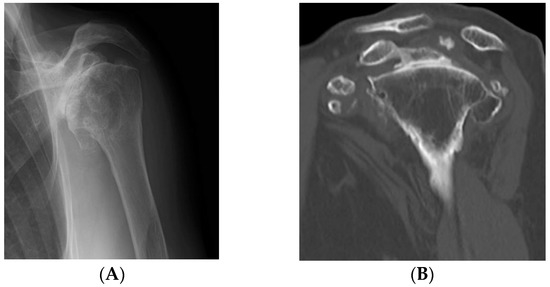

The patient was a 75-year-old woman, who had developed left shoulder pain five years earlier without any known precipitating factor. She presented to our department because of gradual difficulty in raising her left arm and worsening pain. Physical examination on presentation did not reveal any swelling or feeling of heat in the left shoulder. The range of motion of the left shoulder showed extremely severe restriction; namely, flexion 80°, abduction 60°, and external rotation 0°, and prominent impingement symptoms were found. On plain radiographs and computed tomography (CT), prominent shoulder arthropathic changes and numerous calcified lesions around the joint were found. On plain magnetic resonance imaging (MRI), around the shoulder an irregular hypointense region was identified in the center on T1-enhanced images and on T2-enhanced images (Figure 1). Routine blood examinations did not reveal any obvious abnormalities. This patient was diagnosed with synovial osteochondromatosis associated with a massive tear of the rotator cuff and shoulder arthropathic changes, for which the treatment RSA was chosen.

Figure 1.

Preoperative evaluation. (A,B) On plain radiographs and computed tomography (CT), multiple well-demarcated, ossified masses were observed; (C) on three dimensional CT, nodular calcified lesions were similarly present; (D) magnetic resonance imaging (MRI) showed a massive tear of the supraspinatus tendon; (E) on T2-enhanced images, a hypointense mass-like lesion was found. There were many masses in the shoulder subacromium and humeral head space.